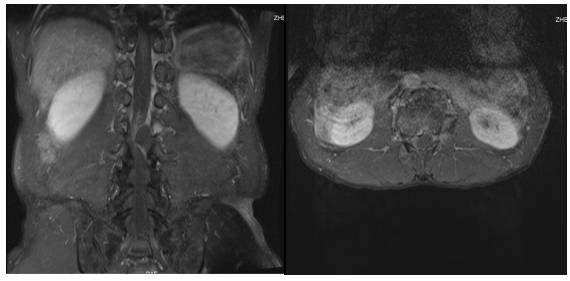

术后次日,患者疼痛症状缓解,左下肢肌力3级,右下肢肌力4级。术后3天患者出院,1个月后回院复查双下肢肌力5级。术后10个月随访患者恢复满意,复查腰椎增强MRI(图5)及腰椎CT(图6)未见囊肿残留及复发征象。

图5. 术后10个月腰椎增强MRI,病灶未见残留及复发,术前马尾神经压迫缓解。

图6. 术后10个月腰椎CT平扫,VRT显示L2左侧上椎板骨质稍缺损。(如箭头所示)